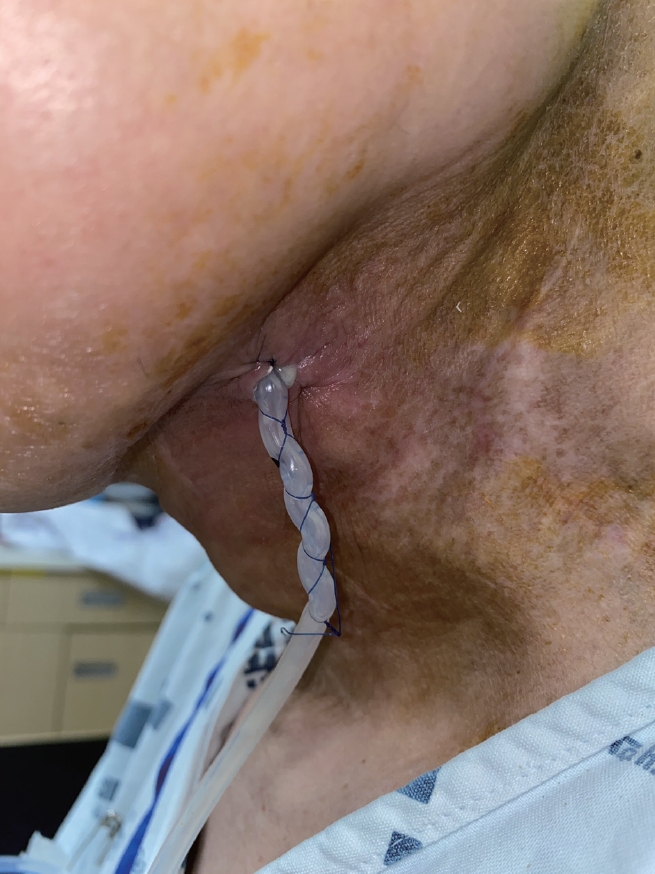

환자는 술후 동시항암방사선 치료 종료 6주 후부터 호흡곤란 증상을 호소하여 방사선으로 인한 후두염 진단하에 3차례 입원 후 보존적인 치료를 하고 퇴원하였다. 이후 정기적 외래 추적 관찰 중 술후 동시항암방사선 치료 종료 후 21주째, 좌측 경부 level II에 작은 피부 결손 부위와 함께 혼탁성삼출물이 흘러나오는 것을 발견하였고, 당시 시행한 경부 전산화단층촬영 검사에서, 이전에는 보이지 않던 좌측 편도와에서 좌측 부인두공간으로 연결된 누공이 새로 형성된 것을 확인하였다(Fig. 3). 이에 따라 국소마취하 절개 배농술을 시행한 뒤, 피부 결손 부위에서 구인두 공간까지 이어지는 누공길(fistulous tract)을 확인한 이후, 배액관의 도관을 재단하고 경부에서 구인두 방향으로 이를 거치하여 지속적 음압 드레싱을 시행하였고, 이와 함께 비영양관 튜브를 통한 식사 및 정맥 내 항생제 치료를 시행하였다(Fig. 4). 치료를 유지하여 1달 뒤 시행한 경부 전산화단층촬영 검사에서 인두피부누공이 호전되지 않은 것을 확인하였고, 이에 따라 전신마취하 대흉근피판을 이용하여 결손 부위를 재건하였다(Fig. 5). 수술후 8일째 금식과 정맥 내 고영양 치료를 유지하던 중, 환자가 협조하지 않아 소량의 경구식이를 시작하였다. 수술 후 12일째 수술 부위 배액관을 통해 다시 타액이 유출되는 것을 확인하여 전신마취하에 경부 탐색술을 시행하였고, 피판 부위는 유지되고 있는 것을 확인하여 죽은조직제거술을 시행한 후 수술을 종료하였다. 환자는 금식을 다시 유지하였고 대흉근 피판재건술 이후 38일째 식도조영술을 시행하였으며, 좌측 이상와 부위에서 작은 누공이 추가로 확인되었으나(Fig. 6), 환자가 경구식이를 강하게 희망하여 2일 후 소량의 경구식이를 재개하였다. 이후 배액관의 배액량이 줄어드는 양상을 보이는데다 환자가 외래 통원치료를 희망하여 입원한 후 80일만에 배액관을 유지한 채로 퇴원하였다.

퇴원 이후 3주째 외래에서 추적 관찰 중, 신체 진찰상 첫 누공 발생 부위와 별도로 좌측 쇄골상 경부 부위의 발적 및 부종이 발견되어 시행한 세침 흡인상 혼탁한 배액이 확인되었다. 전신마취하 경부 탐색술을 시행하였고, 경구강을 통해 인두 부위를 확인하였지만 구인두 부위에는 누공이 의심되는 소견은 보이지 않았다. 피부쪽 누공 입구를 통해 배액관을 삽입 후 지속적인 음압을 유지하며 드레싱 치료와 항생제 치료, 정맥 내 고영양 치료를 시행하였다. 수술 후 8일째 경구식이를 시작하였고, 9일째 식도조영술을 시행한 결과 좌측 이상와의 누공과 함께 동측의 편도와 부위의 작은 누공 입구가 아직 확인되었다(Fig. 7). 수술 후 13일째 압박드레싱을 유지한 채로 퇴원하였다.